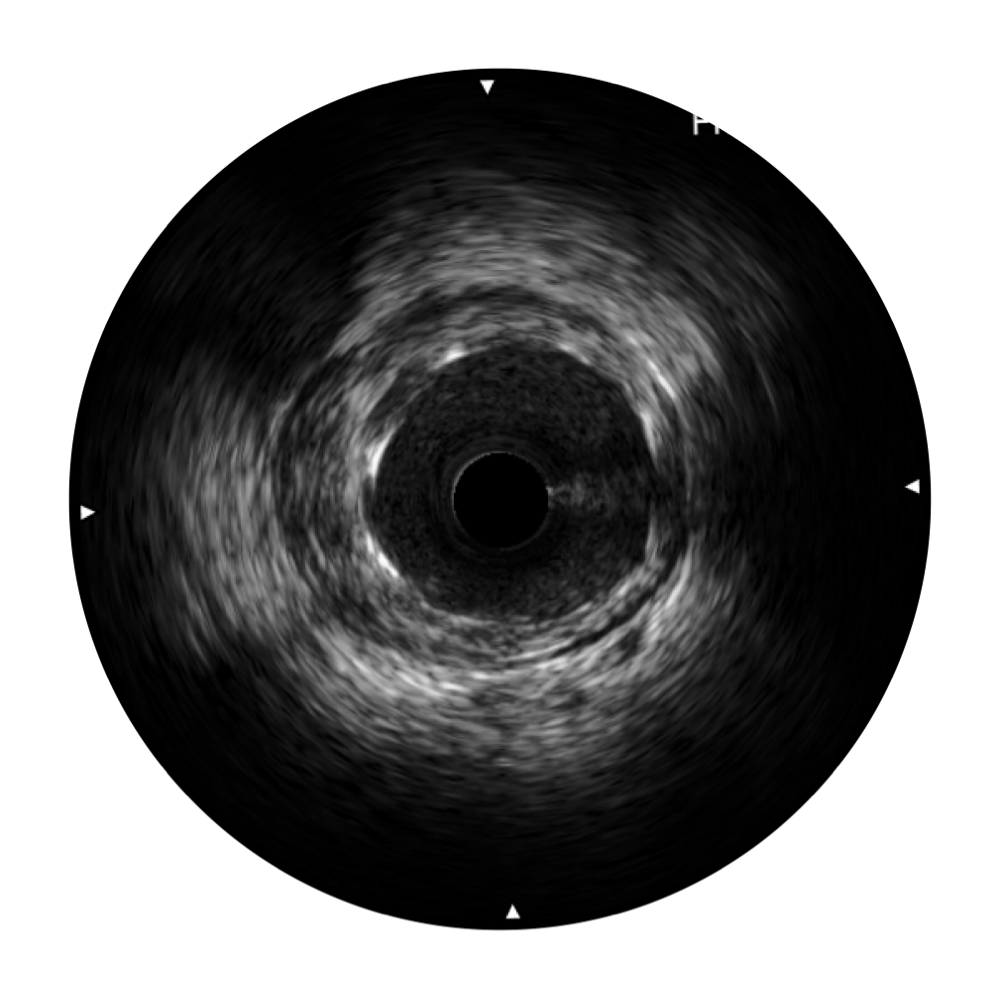

milan米兰宽频IVUS图像

对比传统IVUS导管成像,milan米兰宽频IVUS图像的近场支架梁显影更细腻,远场中膜外血管仍清晰可辨,兼顾远中近,兼顾分辨力与穿透深度